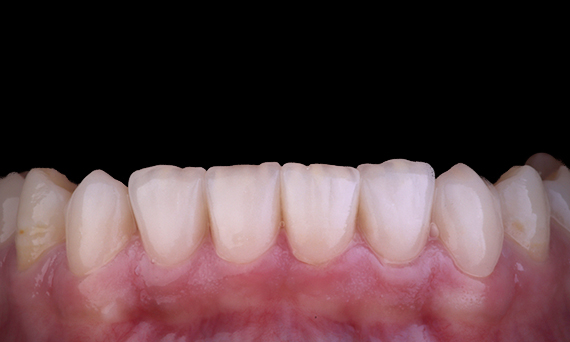

Al considerar el reemplazo de un incisivo central maxilar por una prótesis dental fija implantable, la selección de casos, la planificación y la aplicación meticulosa de métodos de tratamiento son las claves para que la operación sea exitosa. La colocación inmediata del implante y la restauración inmediata pueden minimizar la pérdida de tejido y lograr un resultado altamente estético. La colocación del implante con un enfoque completamente guiado puede mejorar su precisión, y la colocación del pilar o restauración final en el momento de la colocación del implante puede promover la estabilidad del tejido.

Dr. Alan Yap, prostodoncista, Sídney, Australia